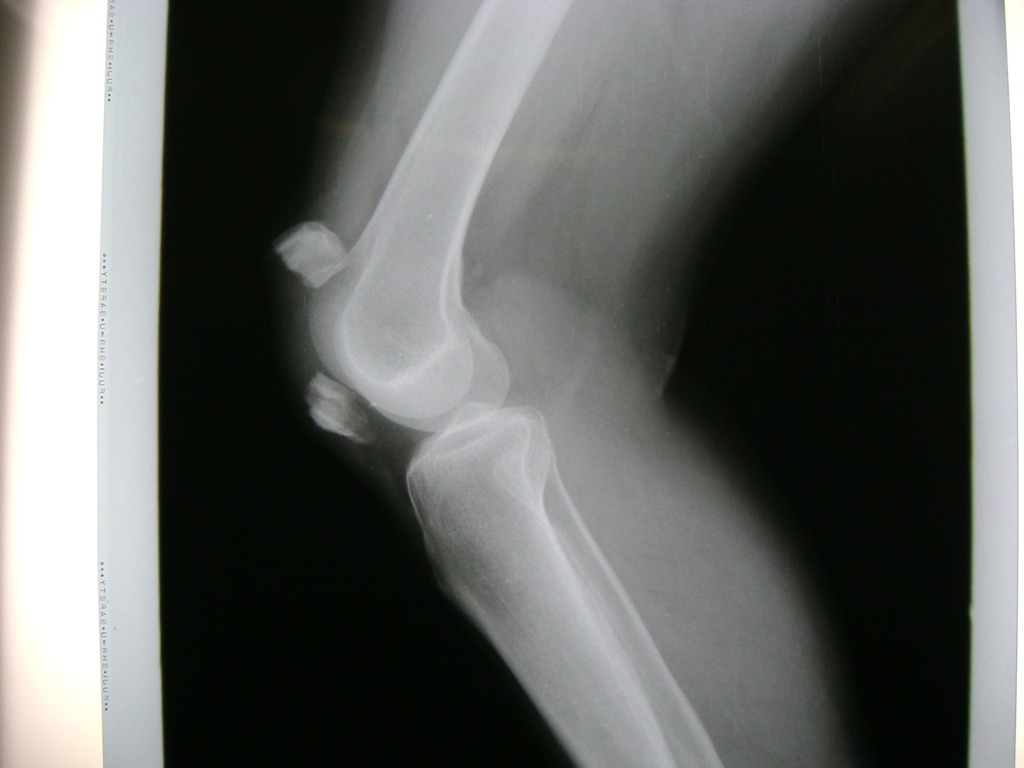

Cirugía de Fémur - Rodilla

La artroscopia de rodilla es un cirugía en el cual la estructura interna de la articulación es examinada ya sea para realizar un diagnostico o para realizar un tratamiento, este procedimiento se realiza utilizando un instrumento parecido a un pequeño tubo llamado artroscopio.